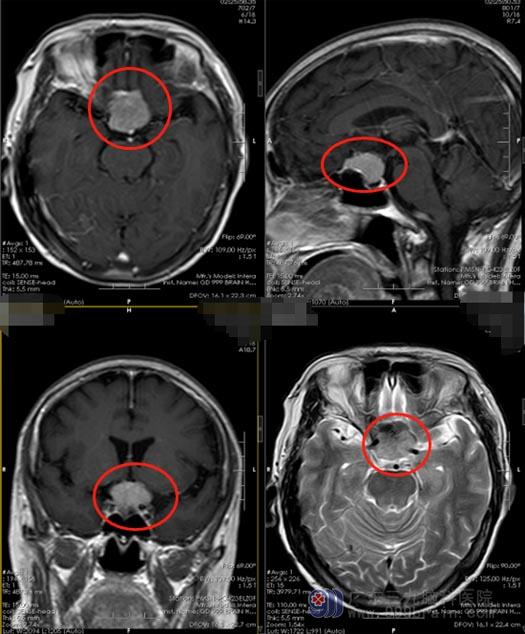

吴阿姨觉得问题有些严重了。当地医院头颅CT检查提示“鞍区一鞍上占位性病变,考虑脑膜瘤”,吴阿姨女儿在网上搜索肿瘤的相关介绍后就更加的恐惧,脑海里一直滚动着这些词:开颅、脑出血、脑积水、脑脊液漏、偏瘫、失明……。一家人忐忑不安地来到广东三九脑科医院,进一步影像检查确诊为“鞍结节脑膜瘤”。

医院副院长、神经外五科主任鲁明向吴阿姨的女儿普及了疾病的相关知识,鞍结节脑膜瘤也称为鞍上脑膜瘤,大约占所有脑膜瘤的3–10%,包括起源于鞍结节、前床突、鞍隔和蝶骨平台的脑膜瘤,肿瘤膨胀生长后可以把垂体柄和垂体推压向后下方,挤压前上方的视神经和视交叉,所以绝大多数鞍结节脑膜瘤的主诉症状为进行性视力下降。最开始的症状主要是视力、视野出现障碍,病程相对是比较缓慢的,双侧的视野和视力的改变往往是不对称,而且有可能会伴有一侧或两侧嗅觉消失,出现嗜睡、焦虑、记忆力减退等精神症状。